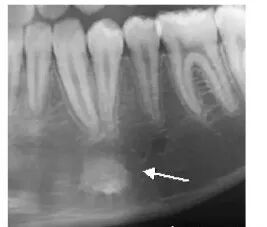

根尖周囊肿

以病原牙尖为中心形成大小不等的圆形或卵圆形、骨质破坏低密度病变区,密度均匀。边缘清晰锐利,周围骨质长期受刺激而在囊肿边缘有致密线条影。可致骨膨隆。